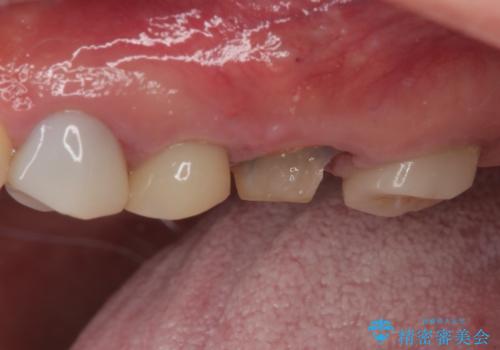

- 奥歯のクラウンが土台ごと外れてしまったとのことで来院された患者様です。

保存可能ではありましたが、予後不良と患者様ご自身が判断されており、相談の結果抜歯即時埋入インプラントによる補綴治療を行うこととしました。